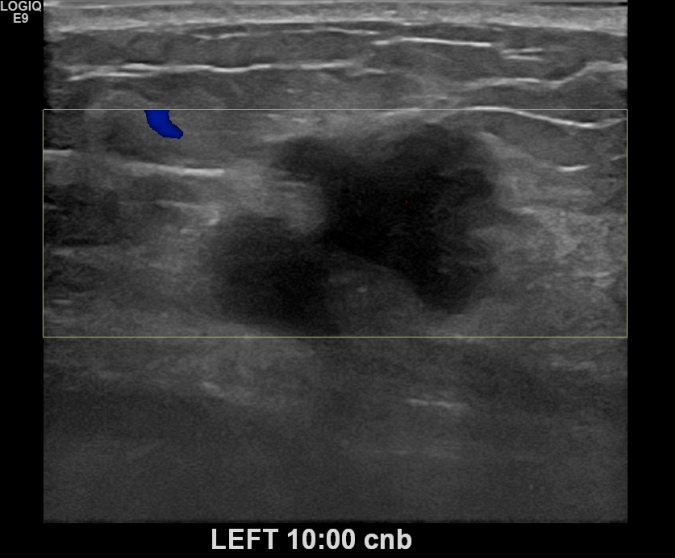

상기환자 건진상 이상소견으로 조직검사권유받고 내원하신 50대 여성분으로 좌측유방멍울  조직검사시행후 유방암 진단되었습니다.